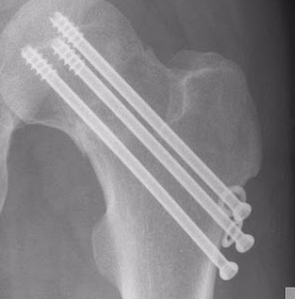

Ich habe 3 parallele Schrauben, genau wie letztes Mal, ist @dr.nicolas.gumpert hier noch aktiv, und hat vielleicht eine Idee oder einen Rat, bezüglich Wattzahlen auf Rolle/Ergo? Operiert wurde das Ganze am 06.07.

Ursächlich dafür ist - bezogen auf meinen ersten Bruch - mit Sicherheit auch die Positionierung der Schrauben. Auch wenn damals, 2011, alle Mediziner sagten, toll operiert (erstes Bild), so erlaube ich mir mittlerweile zu glauben, dass - siehe zweites Bild - in dem "Provinzkrankenhaus" in dem ich nach meinem Sturz gelandet bin, ein besserer Job gemacht wurde. Die Schraubenköpfe sitzen wesentlich bündiger am Knochen, daher spüre ich auch dort nichts reiben oder flipsen. Mag aber vielleicht jemand mit medizinischer Expertise erklären können, warum die beim ersten Mal so weit rausstanden (richtige Schraubenlänge nicht in der Werkzeugkiste?).